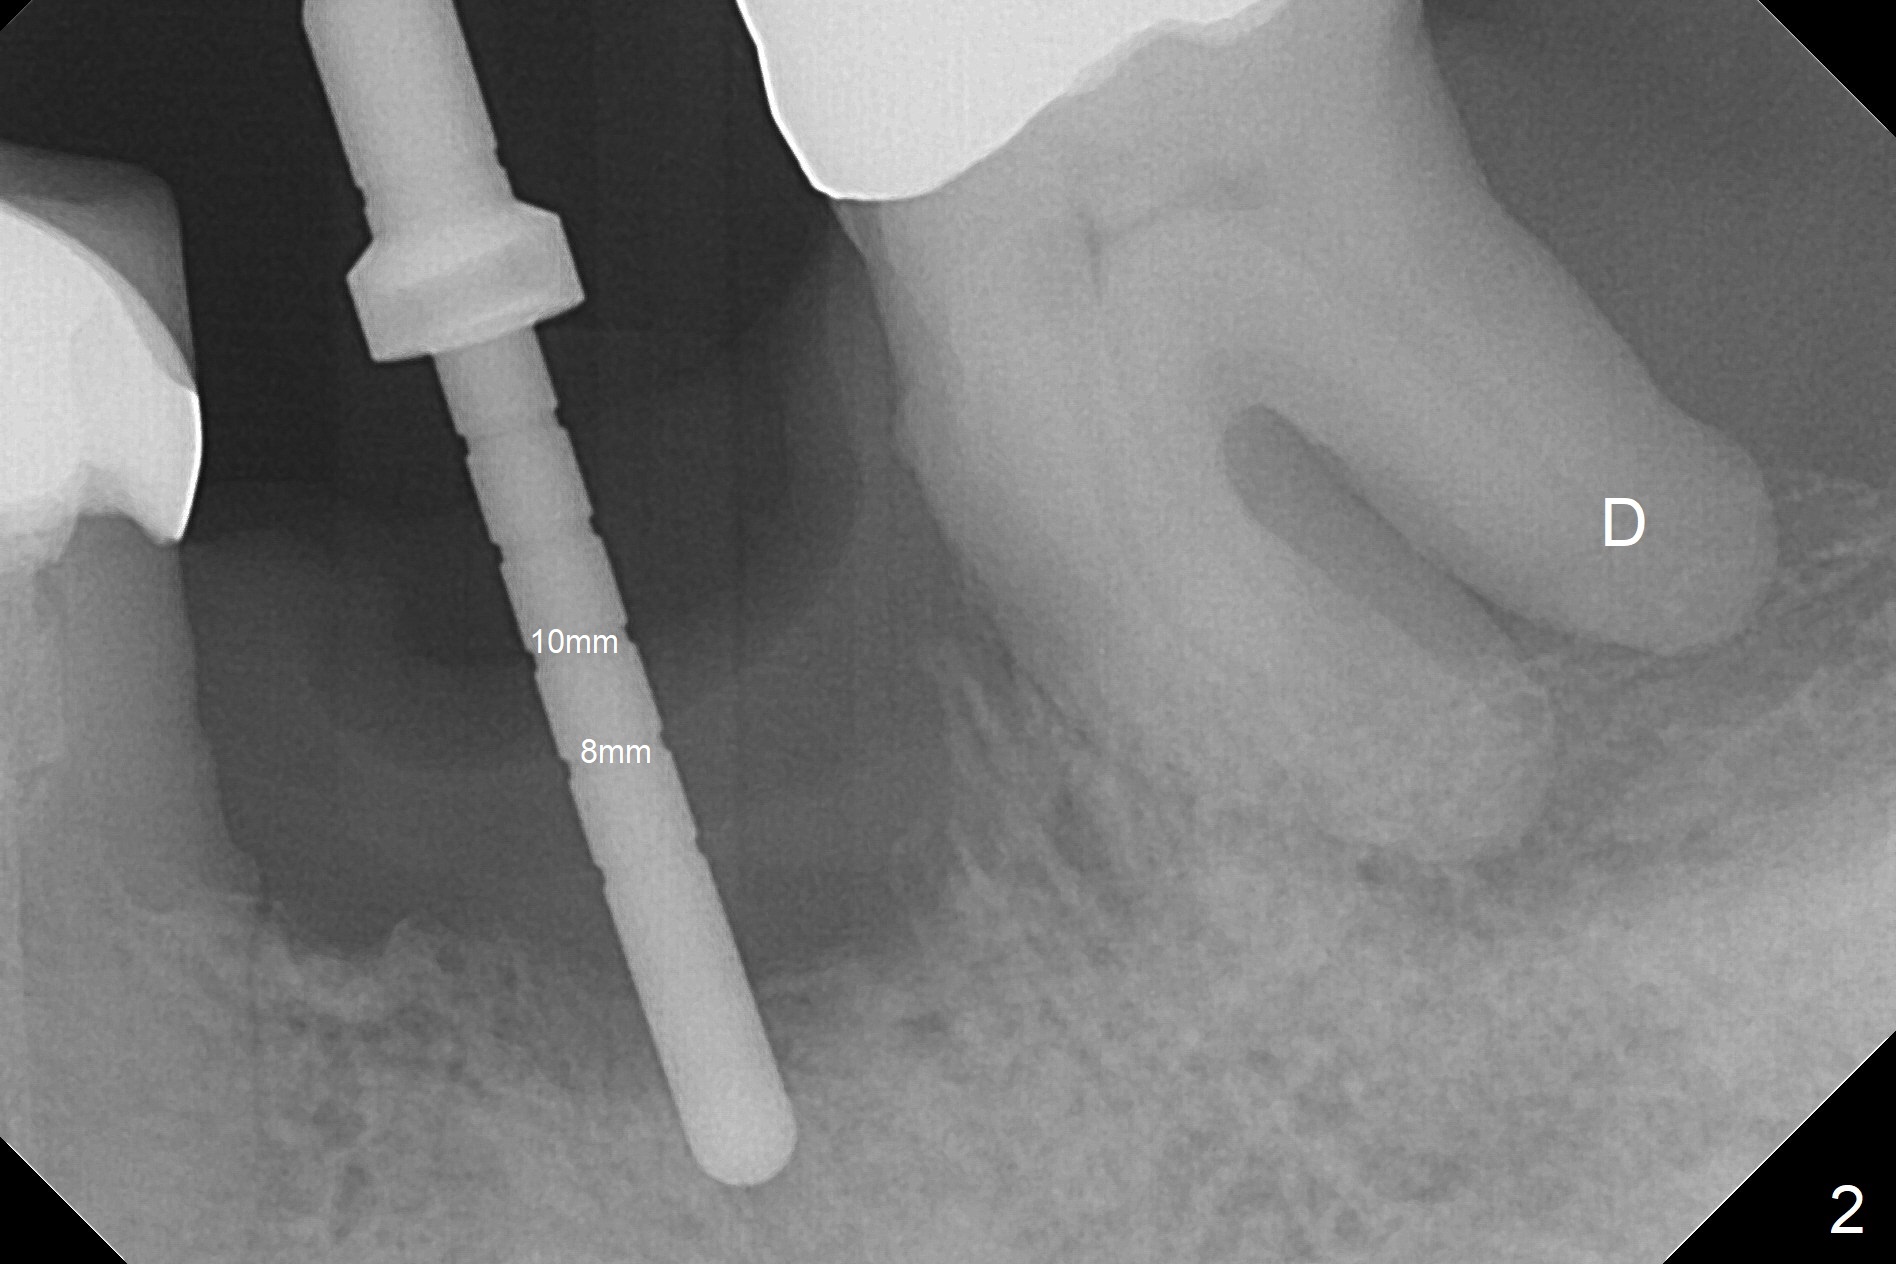

After extraction of the supraerupted tooth #19 with severe buccal gingival recession, the buccal and lingual plate are found to be lost. The sockets are fused and flat without the septum. The bone is hard and painful for the initial osteotomy with infiltration anesthesia (Fig.2). Following block anesthesia, the initial osteotomy depth extends to 8 mm (Fig.3,4). With apparent 4.9 mm clearance, the osteotomy is further extended to 10 mm. The osteotomy walls are apparently intact without severe hemorrhage after each drill. Due to the thick gingiva and severe bone loss, a 5x12 mm implant is intentionally placed 3 mm above the base of the socket bone (Fig.5,6 (yellow dashed line)). Vanilla Cortical and Cancellous allograft (Fig.6 *) is placed around the exposed implant and 7.8x5(6) mm abutment with 4 and 2 mm buccal and lingual gaps. Next collagen plug cut in strip is placed to fill the most coronal aspect of the socket (Fig.7 *). The buccal and lingual gingivae are approximated with sutures proximally. Finally periodontal dressing is applied. Since the Inferior Alveolar Canal is vague in intraop PAs (Fig.4,5), there is worry about potential nerve damage during and after osteotomy. This should be no issue if preop panoramic X-ray is reviewed with measurement (Fig.8). The bone graft appears to remain in place nearly 4 months postop (Fig.9). Two weeks later, he returns for impression. When the provisional is removed, the gingiva is unhealthy. Without the provisional and with improved oral hygiene, the gingiva is healthy one week later, but the tooth #18 is symptomatic. The latter is extracted with socket preservation (Fig.10 *). There is no apparent bone loss around the implant at #19 6.5 months post cementation (Fig.11).